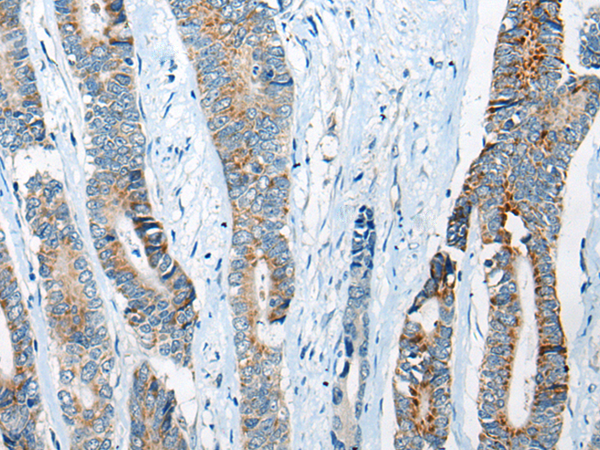

IHC positive control: |

Human brain and human gastric cancer |

IHC Recommend dilution: |

25-100 |